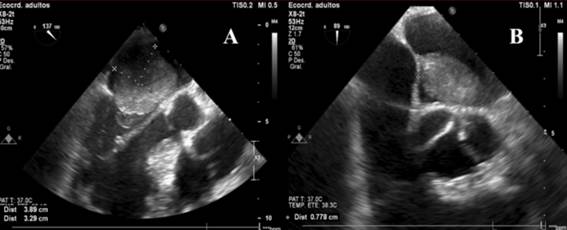

En dicho contexto es valorado por el equipo de cirugía cardíaca y se realiza resección quirúrgica urgente del mixoma con colocación de parche pericárdico a nivel auricular. El ecocardiograma transesofágico intraoperatorio (figura 3) constata la presencia del mixoma auricular y posteriormente confirma el buen resultado quirúrgico, habiéndose logrado extirpar la masa de forma satisfactoria (figura 4). En la evolución se solicitó Holter de 24 horas que informaba un registro ECG incambiado respecto al basal, sin evidencia de bloqueo AV de alto grado o completo. El paciente presentó buena evolución, se mantuvo estable hasta el momento del alta, sin reiterar episodios sincopales ni otra sintomatología de la esfera CV. Se otorgó el alta a domicilio luego de 7 días de posoperatorio.

Figura 3: Ecocardiograma transesofágico intraoperatorio. A) Proyección en eje largo esofágico medio a 137º. Se evidencia una gran masa de 39 x 33 mm, redondeada, de bordes irregulares, a nivel de la aurícula izquierda, que protruye al ventrículo izquierdo en diástole a través de la válvula mitral. B) Proyección en eje corto esofágico medio-superior a 89º. Se evidencia la masa intracardíaca ya mencionada, identificando claramente su pedículo con base de implantación de 8 mm de longitud en el septum interauricular. Las características descritas son compatibles con mixoma auricular.